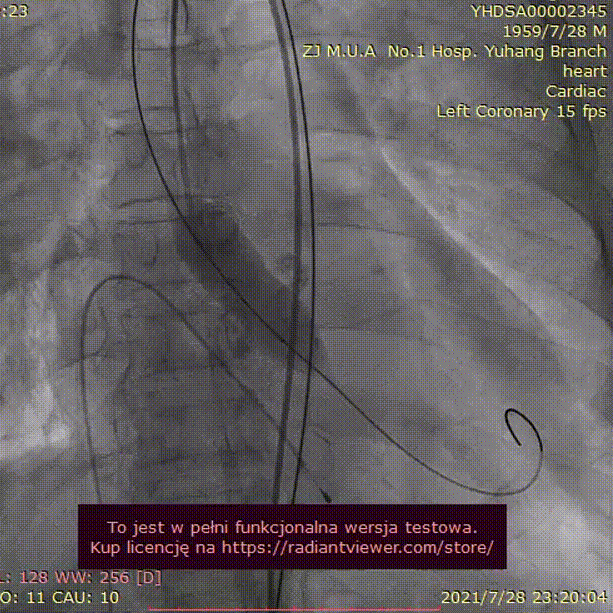

手术过程:

23mm球囊预扩

(有腰征,无瓣周漏,右冠开口阻塞)

TAV24 瓣膜释放前定位

释放4.0*30mm烟囱支架

植入后造影

术后压差1mmHg

术中经食道心超评估: